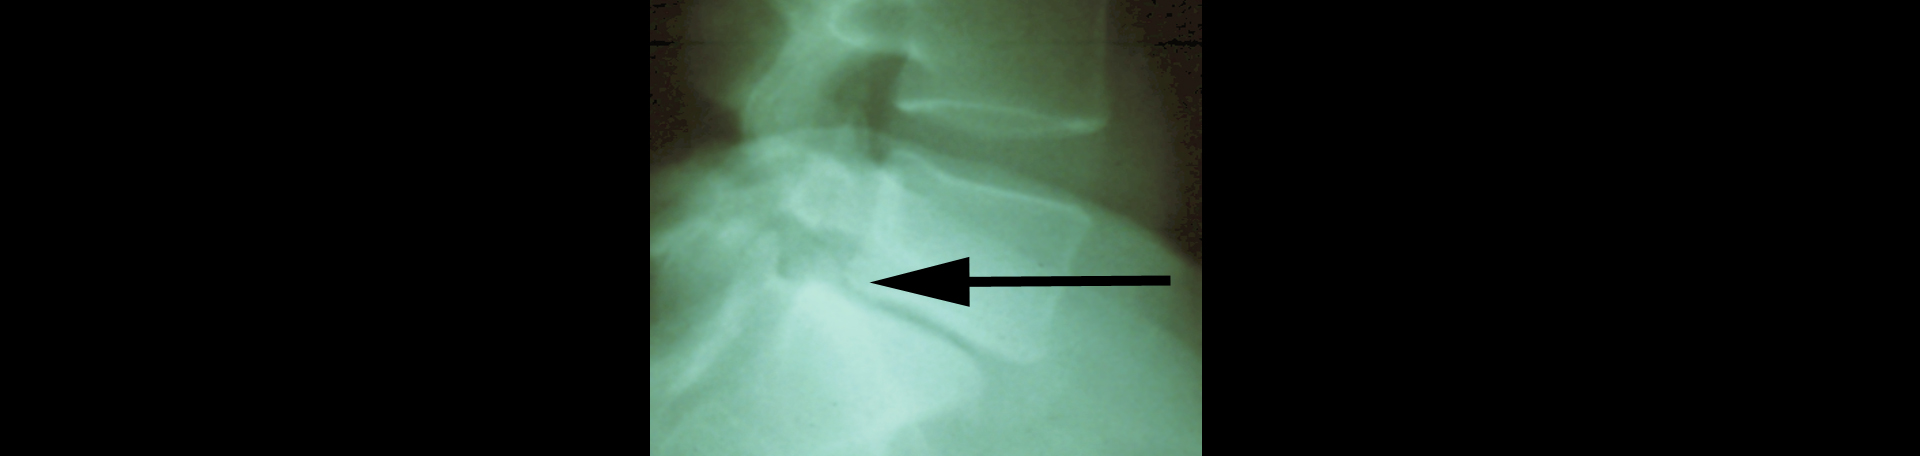

A spinal condition that occurs when one vertebral body (one of the spine’s bones) slips forward or backward on the adjacent vertebral body causing radicular or mechanical symptoms or pain, spondylolisthesis isn’t all that uncommon. Approximately 20% of the adult population has it. Low back pain is its companion. Degenerative spondylolisthesis is most often diagnosed at the L4/5 lumbar spine level in adulthood. Non-degenerative spondylolisthesis typically affects the L5/S1 level. (1) Researchers studied the natural history of degenerative spondylolisthesis and its related slippage by looking through published studies. They uncovered that over a 4 to 25 year timespan, 12% to 20% acquired degenerative spondylolisthesis while 12%-34% of existing degenerative spondylolisthesis progressed. It is valuable to note that 2/3 of spondylolisthesis patients’ slips did not progress. (2) Non-progressing is good! Even degenerative is good as it often responds to care. Your Juneau chiropractor is ready to help with Juneau spondylolisthesis!